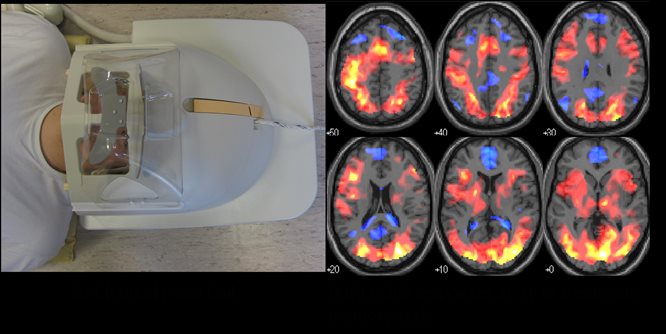

3 Tesla Philips Achieva MRI Scanner

The laboratory is equipped with a 3 Tesla (3T) whole body MR system (Philips Achieva) with multi-transmit and receive capabilities. This enables the lab to offer structural and functional imaging as well as spectroscopic measurement of energy stores and metabolite levels in the brain and body.

Philips Achieva 3T MRI Scanner